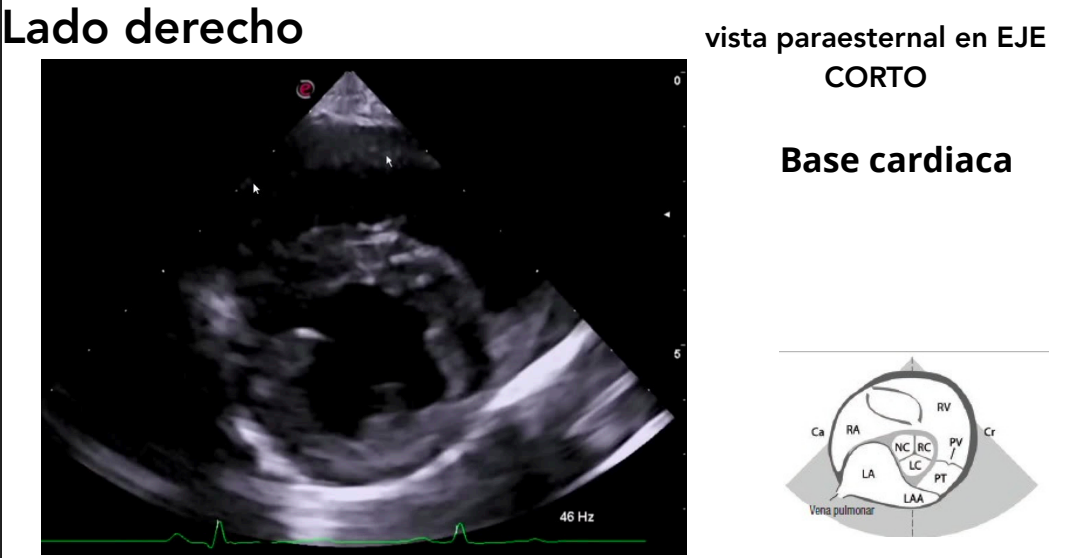

Vista paraesternal en eje corto

- Niveles observables:

- Músculos papilares ("champiñón")

- Válvula mitral ("boca de pez")

- Base cardíaca

- Tracto de salida del ventrículo derecho

Base cardiaca

Muy bueno para buscar mediciones, interesante para ver la dilatación del atrio izquierdo al compararlo con el de la aorta